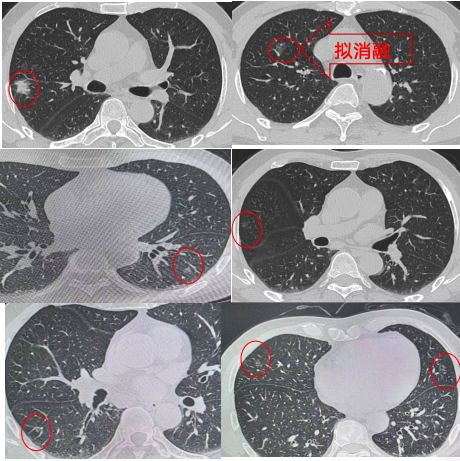

近日,我院胸外科刘伦旭教授、蒲强教授、廖虎副教授团队成功为一名患有双侧多发肺结节老年患者实施“杂交”手术。该手术结合了射频消融和胸腔镜下微创手术两种术式,一次性解决了患者肺部的多发“高危”结节,同时最大限度地保留了肺功能,术后患者生命体征恢复平稳,术后2天即出院。经过文献检索,这也是我国西部地区首例射频消融和胸腔镜下微创“杂交”手术。

患者杨先生68岁,2月前因咳嗽于当地医院就诊行胸部CT检查发现双肺多发结节,最大者位于右肺上叶后段,大小约2.3cm*1.7cm,所有结节临床评估均考虑为早癌或癌前病变。

围绕患者病情,团队开展了全科讨论:患者右肺多发结节,部分肺结节的位置较深,若按照传统外科手术方法需要进行右肺上叶+中叶切除+右肺下叶部分切除,还需要对患者左肺的结节也进行二期手术。然而患者既往存在有多种合并症,如中-重度阻塞性通气功能障碍等,肺功能较差,同时进行多个肺叶切除,其肺功能将无法耐受,对侧的结节也将丧失手术的机会。

患者病情特殊,考验着胸外科医生术前手术方案的设计、术中手术操作,以及术后监护管理。刘伦旭教授、蒲强教授、廖虎副教授团队决定尝试采用一种创新的“杂交”手术,即对危险性较低的磨玻璃结节,选择行射频消融,以减少对患者的创伤;而对右肺上叶后段较大的、危险性更大的结节,选择胸腔镜微创手术切除右肺上叶后段肺组织。

团队与患者及家属进行了充分沟通,并进行了扎实的术前准备,包括穿刺方案,消融方案,及术中可能遇到的并发症及应对措施,以及术后并发症的预防和处置方案等。8月15日,手术按计划进行。患者全麻后,廖虎副教授首先根据移动CT扫描引导下行经皮消融针穿刺,穿刺成功后行射频消融治疗。随后,立刻改变体位为患者行单孔荧光胸腔镜右肺上叶后段切除+右肺中叶楔形切除+右肺下叶楔形切除。术后经过观察,无特殊不适,安全返回病房。术后第一天复查胸片无特殊,术后第2天引流较少,即安排拔管出院,由于保留了足够的肺组织,患者术后运动耐量良好,经初步评估可耐受对侧手术。

随着人们健康意识的增强及低剂量胸部CT筛查的普及,越来越多的肺结节被发现,其中肺多发结节的处理一直是困扰着患者和医生的难题,国际及国内的专家共识都主张在最大限量保留患者肺功能的前提下,尽量处理更多的高危结节。体积较大、恶性程度高的结节通过微创手术切除;体积较小、恶性程度低、位置较深导致切除范围大的结节通过介入消融治疗的策略,得到越来越多的医生及患者的认可。全身麻醉胸腔镜微创手术的同时行肺结节消融术,将两种术式联合进行,一次性完成多发肺结节的诊断和治疗,有效减少手术创伤,完美解决患者肺功能无法耐受双侧肺手术的问题。本次胸外科完成“杂交”手术,充分展现了华西医院胸外科的巨大技术优势和以人为本的治疗理念。